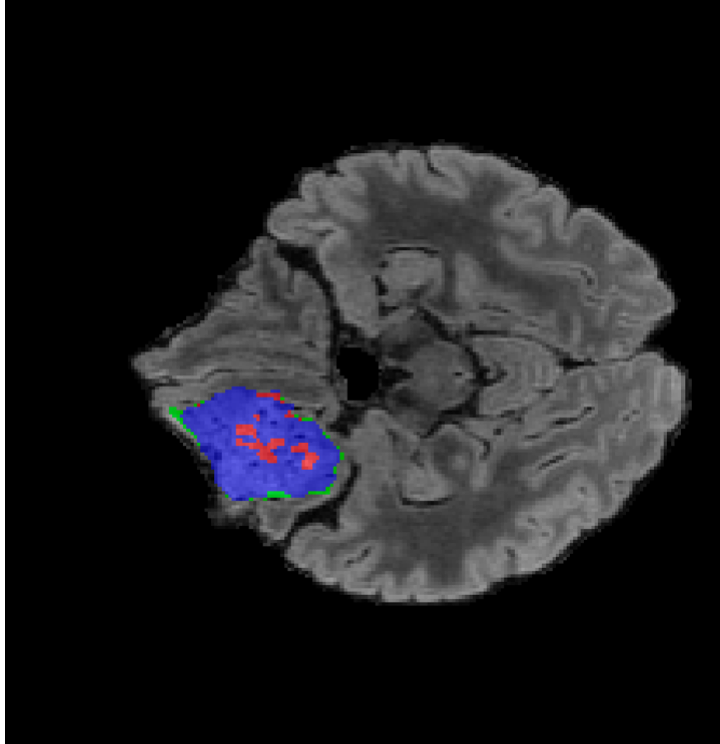

Tumour Information Preservation. For the brain tumor segmentation, we use a Swin UNETR model[28, 70], trained with random rotation, and intensity as data augmentation. On the test set with human ground-truth annotations (), the brain volumes generated from single slice input preserve the volume of the different tumour components (paired t-test, for all 3 classes). In Figure 4, we highlight the tumor profiles of the generated MRIs compared to the ground truth tumour profile. The real MRI Dice score in the test set is 85.15 while the generated MRIs from a single slice have a dice score of 83.09. This shows how the generated MRIs indeed preserve the tumor information and can act as an affordable and informative pseudo-MRI, before conducting an actual costly MRI examination in hospitals. More detailed results are provided in supplementary material.

Leveraging Context. Since we train on a predominantly cancerous brain dataset, one question that might arise is whether X-Diffusion generated MRIs preserve tumour information when the given inputs do not intersect with any tumour. We perform experiments varying the input slice index used to generate the 3D brain MRIs and measure the performance for input slices with no intersection with the tumour (not a single pixel with tumor label in the input slice). We also measure performance when only input slices are selected from tumor range. The Dice Scores of the random slices, no-tumour, and only-tumour are 83.09, 79.23, and 83.68 respectively. As can be seen here, the brain volumes generated from input slices with no tumour still preserve tumour information in reconstructed brain volumes despite a small drop in performance. This indicates that X-Diffusion is leveraging the context to preserve key information, such as tumor locations. This observation is consistent with how tumor segmentation models with global context [13] perform better than local-based U-Nets. More details are provided in supplementary material.

To see when and how X-Diffusion fails, we conducted an experiment on healthy brains (no tumour) using IXI dataset, by running an X-diffusion trained on BRATS brain tumor dataset. Our X-Diffusion achieved a PSNR of 35.86 dB on the IXI dataset despite being trained on the BRATS dataset. We then ran the tumour segmenter on the set of 582 healthy scans and corresponding generated MRIs. The segmenter predicted tumours in 9.9% of the real healthy brains and in 11.3% of the generated brain MRIs. Some of these tumor hallucination examples fron X-Diffusion generation are shown in Figure 10.